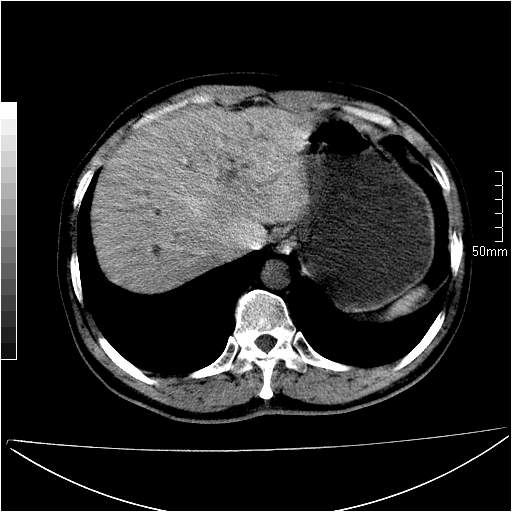

男性,54岁,皮肤黄染,搔痒一周余.b超示肝左叶回声异常.初步诊断1胆总管下段结石2胆囊结石伴慢性胆囊炎请各位战友帮忙看一下肝脏多发低密度如何解释恰当.增强效果不是很好.请大家见谅.

胆总管及肝内胆管扩张,考虑是结石!但,肝内的低密度区增强不明,可能是肝ca,因为肝ca在增强时呈快进快出.另年胆总管扩张原因,可以考虑一下是不是,胆管ca.再次要考虑肝内的低密度是否为海绵状血管瘤所致!

首先,胆总管下端结石梗阻伴肝内胆管扩张可确定。

其次,增强动脉期肝静脉显影,肝实质密度不均。——此为右心功能不全引起肝淤血的表现。

另外,肝八段低密度占位,呈多灶性,考虑肝脓肿或肝癌可能,(图像质量欠佳)建议进一步检查。